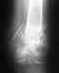

7 апреля этого года я получила оскольчатый перелом пяточной кости, неврит большеберцового нерва и обширный некроз на пятке. Перелом давно зажил, уменьшался и заживал некроз до тех пор, пока я не стала ходить без костылей. С этого момента под некрозом началось воспаление. Сейчас я 4 неделю лежу в гнойной хирургии. Некротическую ткань сняли, но нагноение не проходит и рана не уменьшается. Лечение: перевязки с полуспиртовым раствором, мазь Вишневского на 2 дня, кварцевание.Но ведь этим методам 30-40 лет, неужели нет более действенных новых разработок в гнойной хирургии. Сколько же мне придется лечить свою ногу таким способом?Очень надеюсь на ответ и заранее благодарю.Суважением, Марина.

Остеомиелит пятки довольно трудная проблема. "Магических" новых средств не существует. Участки омертвевшей кости являются субстратом для патогенной микрофлоры, доступ любым лекарствам туда затруднен, поскольку эти зоны не кровоснабжаются. Так что в основном надо полагаться на местные меры по санации - повторные обработки гнойного очага с удалением нежизнеспособных и инфицированных тканей. После ликвидации очага инфекции замещать дефект.